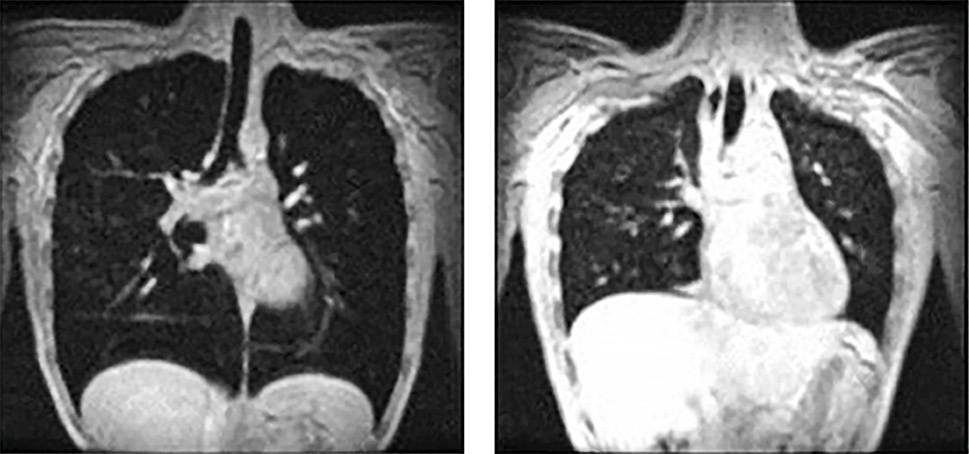

3.2.3. Динамическая МРТ

Динамическая МРТ является одним из наиболее информативных и точных визуализационных методов, позволяющих оценить экскурсию и степень утолщения различных отделов диафрагмы в разные фазы дыхательного цикла и при проведении специальных проб. Во многом благодаря данному методу были проведены замеры на здоровых добровольцах и созданы таблицы нормальных значений параметров диафрагмы, а также удалось подтвердить участие диафрагмы в стабилизации поясничного отдела позвоночника при произвольных движениях туловища и конечностей [18]. Из минусов данного метода диагностики стоит упомянуть ограниченную доступность и высокую стоимость исследования, а также его длительность (до 40 минут), что в некоторых случаях может быть препятствием его применения у постинсультных пациентов. Применение МРТ также ограничено у пациентов с металлическими имплантами и клаустрофобией [18] (рис. 4).

Рис. 4. Магнитно-резонансное изображение при максимальном вдохе и максимальном выдохе при 12-секундной задержке дыхания у здорового добровольца [18]

Fig. 4. Magnetic resonance images at maximum inhalation and maximum exhalation during 12-s inspiratory breath-hold (healthy volunteer) [18]